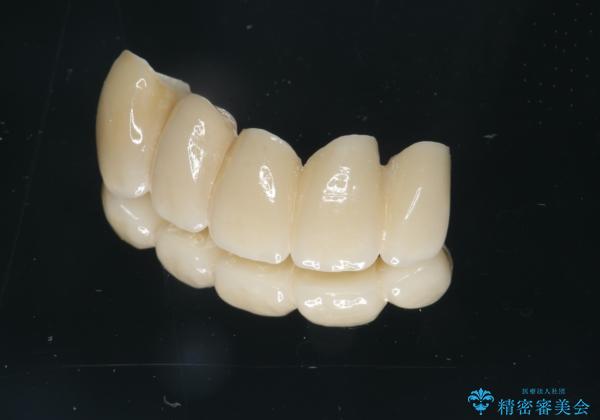

セラミック治療を行う前に歯周病の問題を解決すべく歯周外科を行い歯周ポケットを除去し整備したのちセラミックブリッジ・クラウンの製作を行います。